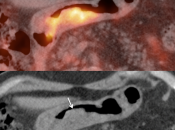

False Negatives:

• Lesions less than 8.0 mm: These very small lesions (primary or metastatic) may have minimal or no appreciable uptake, as they are “beneath the resolution of PET”.

• Poorly-Avid Primary Subtypes:

• Mucinous carcinomas

• Signet ring cell carcinoma

• Poorly differentiated adenocarcinomas

• Small FDG-avid perigastric nodes can be masked by superimposed uptake from the primary lesion.